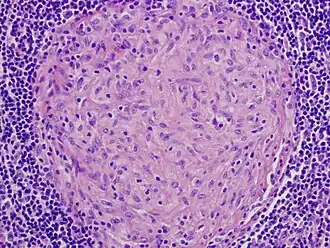

En médecine, « granulome » est un terme assez général désignant de petites papules érythémateuses ou tumeurs vasculaires inflammatoires ou diverses formes d'amas de cellules épithélioïdes entourés de lymphocytes, qui apparaissent sur la peau, des muqueuses ou dans les organes internes (éventuellement autour d'un corps étranger).

- petit agrégat nodulaire constitué de cellules mononucléées inflammatoires ;

- agrégat de macrophages modifiés ressemblant à des cellules épithéliales. Ce type de granulome est souvent bordé de lymphocytes porteurs de cellules géantes multinucléées.

Son nom évoque sa forme la plus fréquente en forme de grain, mais il prend parfois l'apparence de plaques. Dans certains cas, il peut y avoir présence de pus (neutrophiles et macrophages en grande quantité).

Certains granulomes renferment des éosinophiles ainsi que des cellules plasmatiques[2].

Une fibrose borde souvent la périphérie de la lésion[2].

- Les granulomes épithélioïdes (ou tuberculoïdes) ; ce sont des formes dont les contours histologiques sont mal limités. Ils sont classés en granulomes caséeux (tuberculose) et granulomes non caséeux (sarcoïdose par exemple, aux contours plus nettement limités à l'histologie)[15].